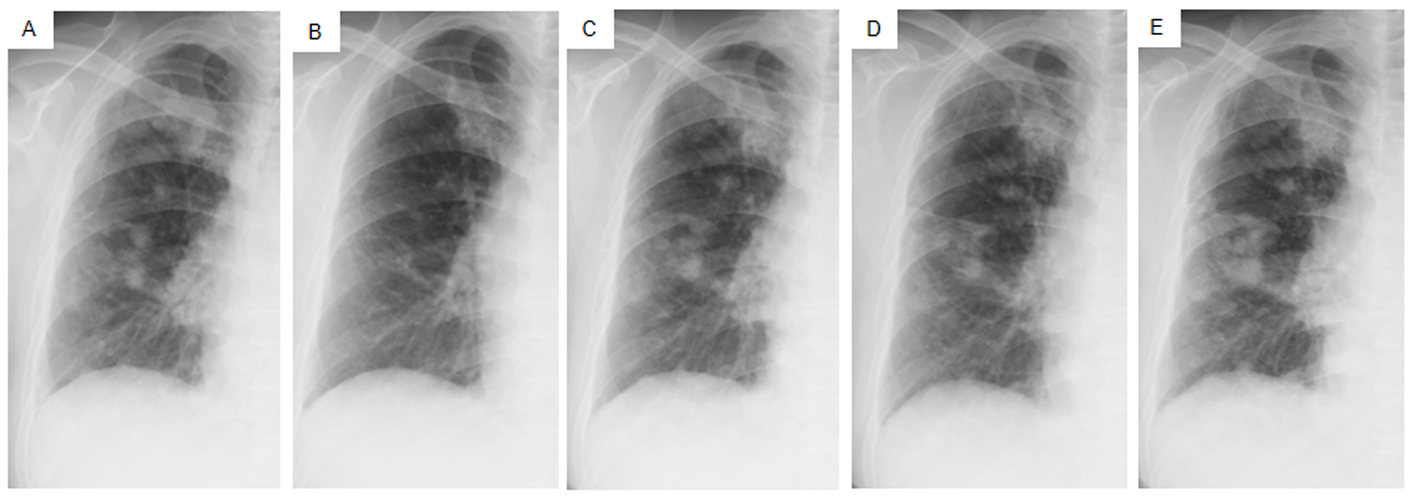

Daily treatment with gefitinib (250 mg/day) as the second-line regimen induced a remarkable tumor reduction seen on chest X-ray film within the initial 1.5 months of gefitinib treatment (Fig. 4A, B), but treatment was suspended for 3 weeks because of grade 3 elevation of alanine aminotransferase levels. Gefitinib treatment was resumed on alternate days because of recovery of abnormal hepatic function and rapid progression of lung tumor on chest X-ray (Fig. 4C). However, alternative day administration of gefitinib did not respond (Fig. 4D). We eventually documented progressive disease (PD) 4.5 months later (Fig. 4E). During this period, serum amylase levels initially decreased, but gradually increased up to 465 IU/L after gefitinib treatment was suspended (Fig. 2). Amylase isozyme patterns kept the salivary type as the most abundant (79% in March 2011, at the beginning of gefitinib, and 93% in mid-August 2011, 6 days after the discontinuation of gefitinib). In August 2011, after documentation of PD following gefitinib treatment, we obtained a bronchoscopical specimen of a new endotracheal metastasis, while neither bronchoscopical biopsy of intrapulmonary metastases nor surgically resected biopsy of a slightly enlarged cervical lymph node harvested cancerous tissue. PNA-LNA PCR clamp analysis of the endotracheal specimen revealed that the EGFR L858R point mutation was present; however, secondary EGFR mutations such as EGFR T790M were not detected. Furthermore, staining was negative to slightly positive and scattered when the sections were reacted with the anti-salivary type amylase antibody (Fig. 3E), and immunohistochemical analysis using the mutant-specific antibody detected positive expression of the EGFR L858R mutant (Fig. 3F). Docetaxel, pemetrexed and erlotinib were used as the third-, fourth- and fifth-line regimens and a second trial of carboplatin plus paclitaxel was used as the sixth-line regimen. Erlotinib, another EGFR-TKI, only maintained stable disease for 6 months. The patient died of lung cancer in September 2013 at 3.5 years after referral.

![]() Click for large image | Figure 4. Chest X-ray films of the right lung field taken late in March 2011 before the administration of gefitinib (A), taken early in May at 1.5 months after initiating gefitinib and just before the suspension of gefitinib due to grade 3 elevation of alanine aminotransferase levels (B), taken early in June at the resumption of gefitinib on alternative days (C), taken in mid-July at the 1.5 months after the resumption of gefitinib (D), taken in mid-August after the documentation of progressive disease and 4 days after discontinuation of gefitinib (E). |